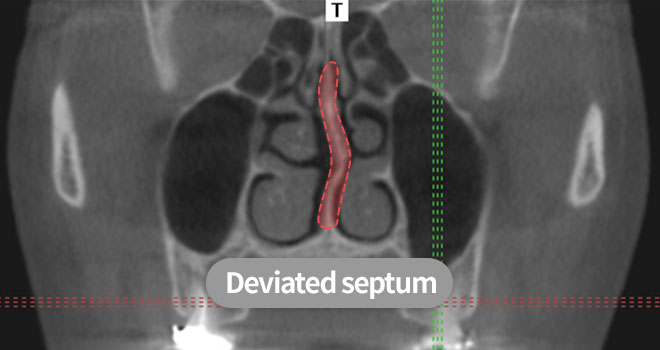

A deviated nose is a case in which the nose's bridge is curved or crooked to one side.

Most patients with a deviated nose have a crooked shape and a deviated septum that needs to be corrected simultaneously for both aesthetic and functional reasons.

Deviated septal cartilage

When the septal cartilage -which acts as a wall that separates the nostrils- is bent, causing aesthetic and functional discomfort

Most deviated noses are accompanied by a visible external nasal deviation and internal septal deviation.

If only the curvature of the external nasal surface is corrected, the deviation is highly likely to recur and cause functional discomfort such as breathing difficulties.

Therefore a septal correction should be performed simultaneously following a precise diagnosis.